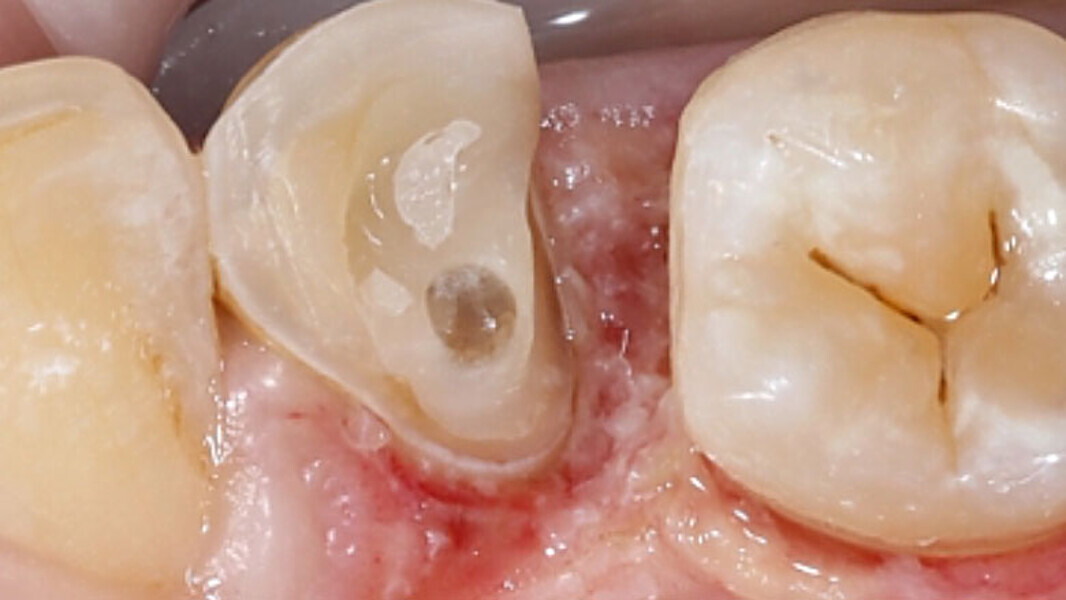

Fig. 11. La restauración de cerámica de feldespato durante la prueba clínica en boca.